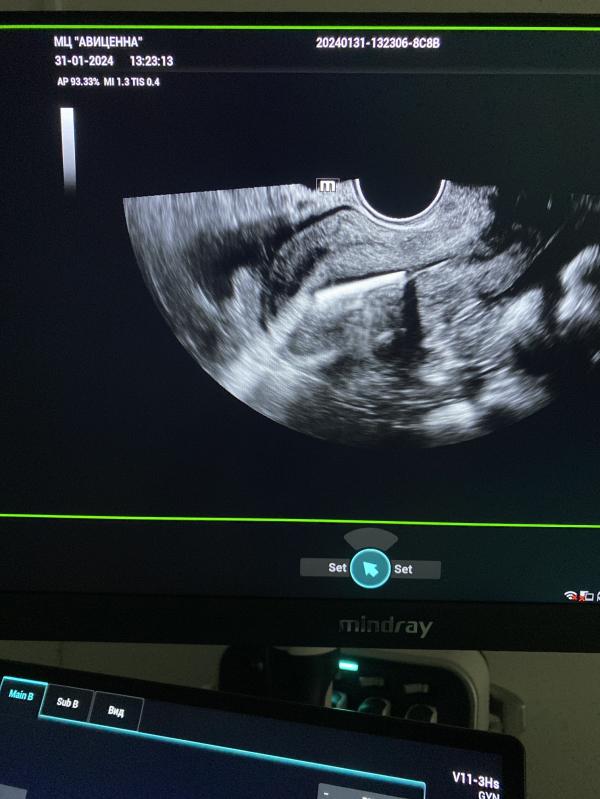

Спираль в полости матки ( белый стержень) после установки проходит 3 года. Стоит отлично 👍🏼.